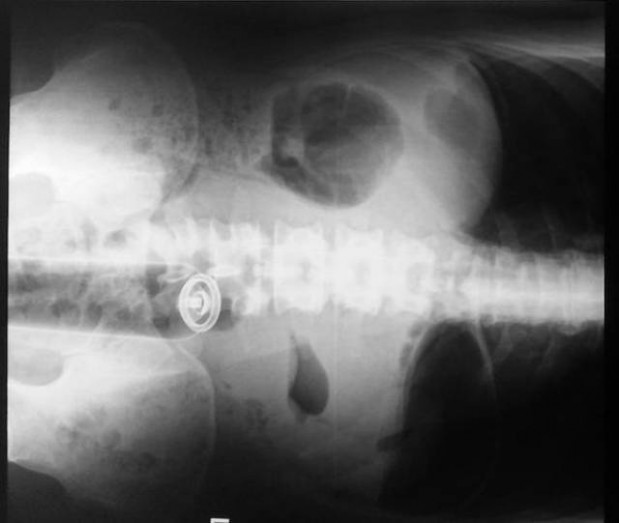

On suorastaan käsittämätöntä katsoa millaisia esineitä ihmiset nielevät ja tunkevat alapään kautta sisään. Röntgenosastolla työskentelevillä lääkäreillä on varmasti aika ajoin naurussa pidättelemistä, kun he löytävät alapäästä viinipulloja, kesäkurpitsoja ja jopa munakoisoja! Ihmiset ovat todella erikoisia varsinkin silloin, kun he yrittävät tyydyttää halunsa. Mukana on myös kuvia tapauksista, jotka sattuivat täysin vahingossa.#1 Naisen vatsasta löytyi 78 ruokailuvälinettä

#10 Miehen jumissa oleva seksilelu ja pihdit, joilla hän yritti saada sen pois